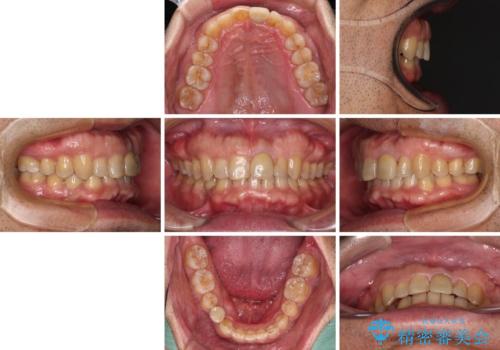

- 上下前歯のデコボコと下顎小臼歯の欠損によるスペースを気にして来院された患者様です。

下顎は左右1本ずつ小臼歯が欠損しており、右側にはやや大きな欠損がありました。

欠損により下顎歯列は相対的に小さく、上顎に深く咬みこんでしまうディープバイトとなっていました。

インビザラインによる治療を希望されたため、左側のスペースは閉じ、右側はスペースをより拡大し、インプラント補綴を行うこととしました。

咬合力が強く、インビザラインのみではディープバイトを改善することができず、半年間ほどワイヤー装置による矯正治療を行いました。

インプラントの埋入は矯正治療中に行い、矯正治療後はインプラント上補綴および、前歯のセラミック治療を行いました。